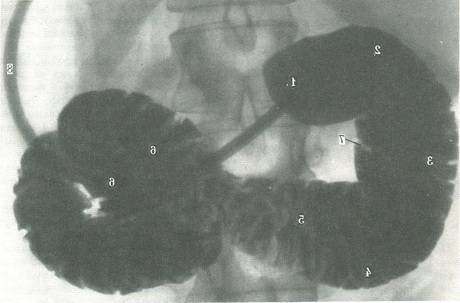

248. Рентгенограма дванадцятипалої кишки, що знаходиться в стані гіпотонії (по Л. Д. Линденбратену).

1 - цибулина; 2 - верхня масть; 3 - верхній вигин; 4 - низхідна частина; 5 - нижня частина; 6 - дванадцятипалій-худа кривизна; 7 - область двенадцатиперстного соска; 8 - зонд, через який вводили контрастну речовину.